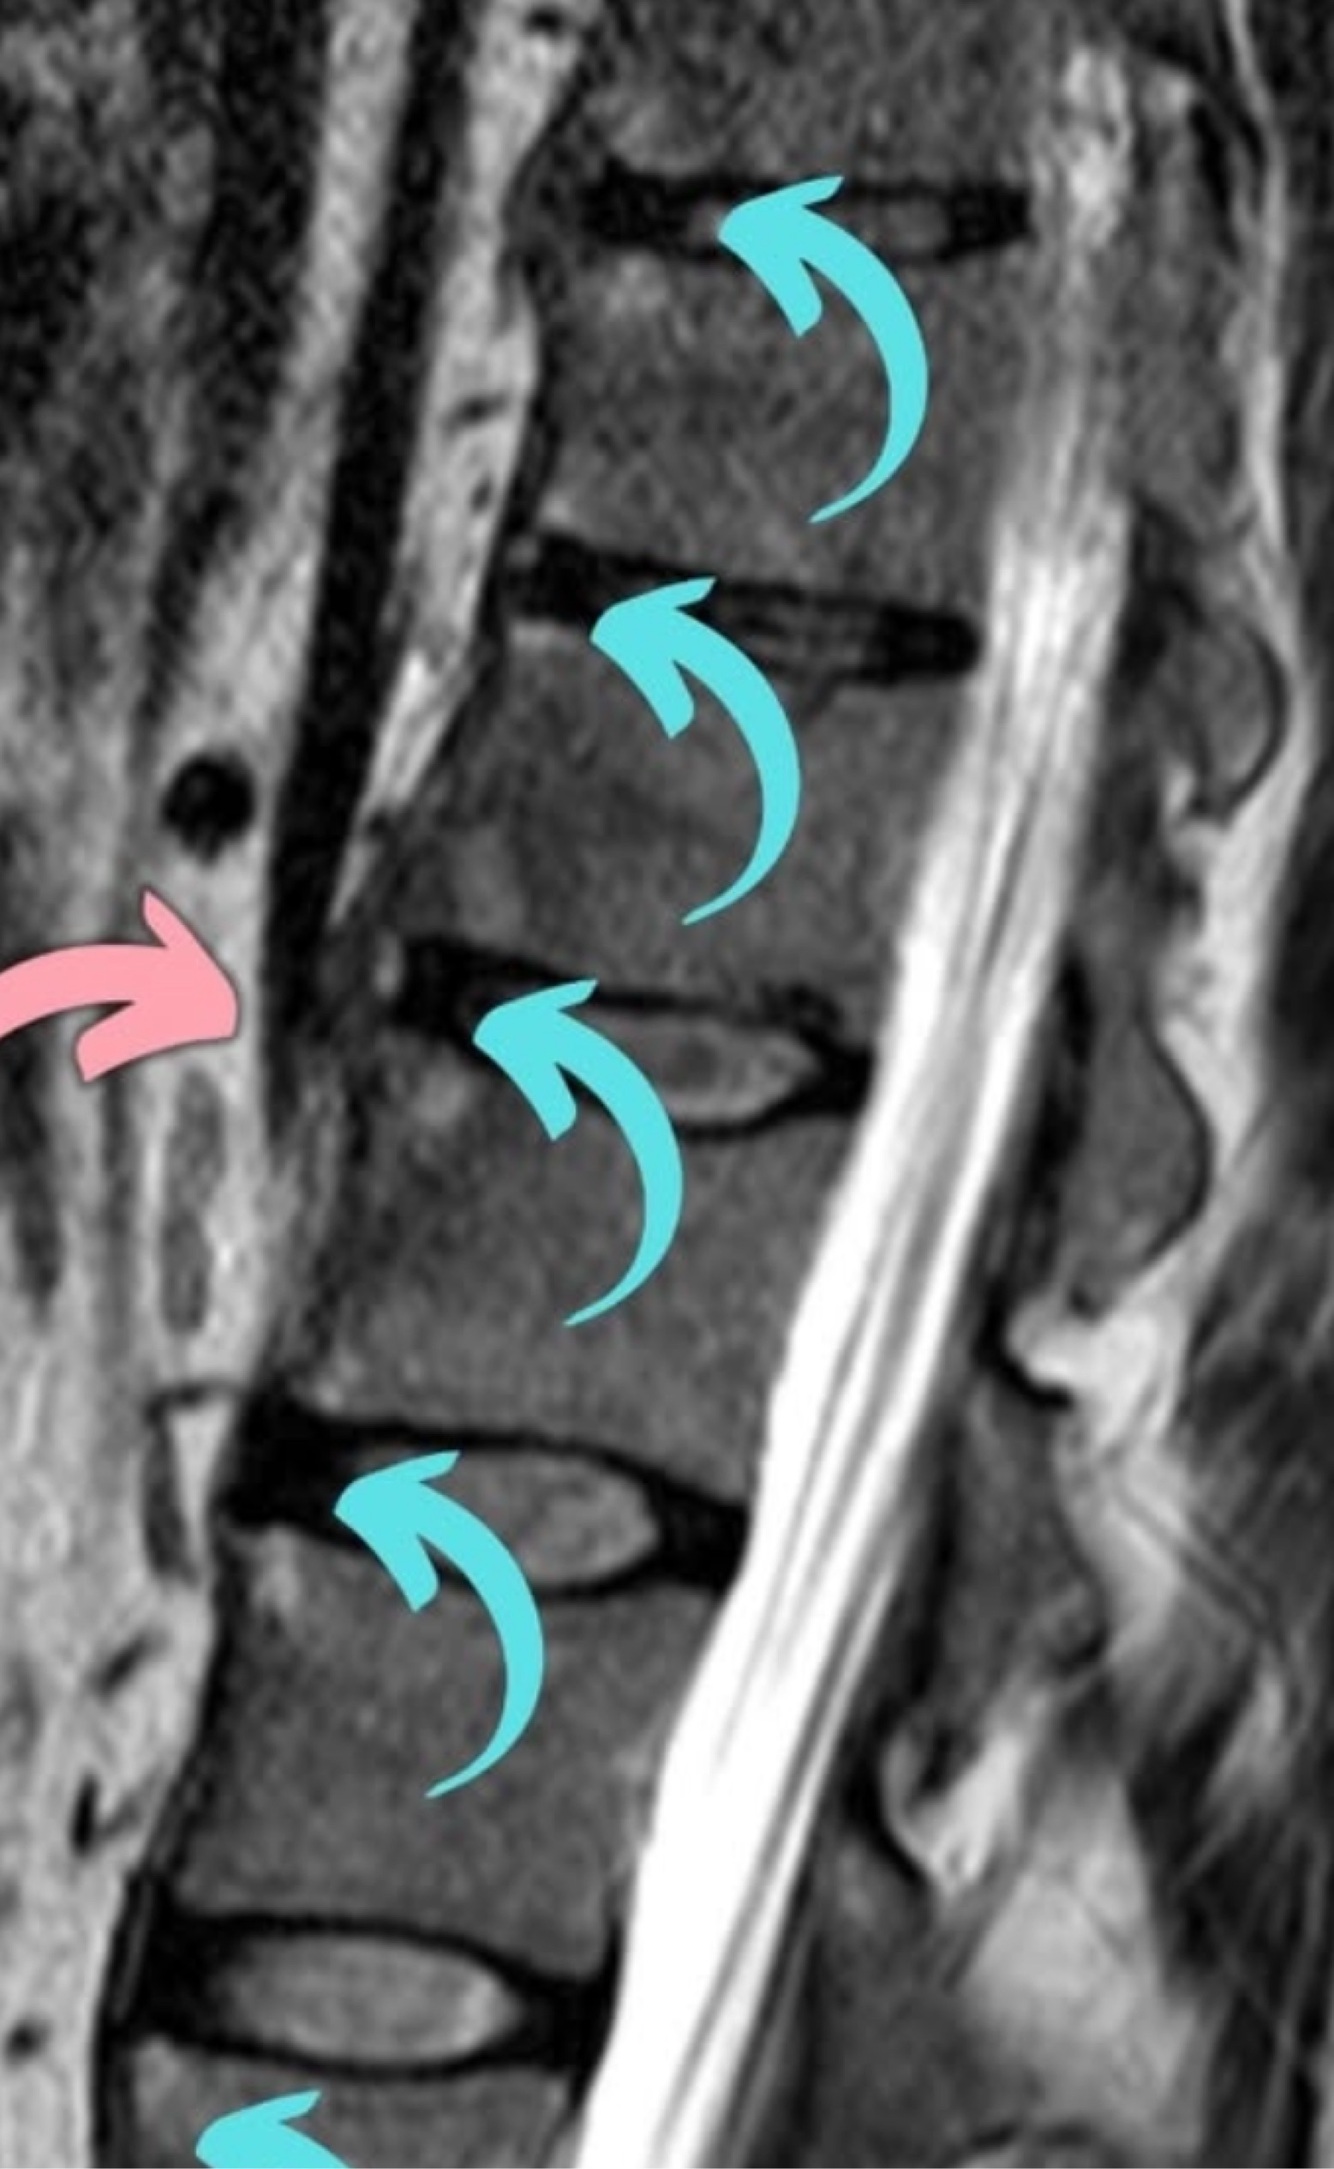

Qual o diagnóstico?

A

Vértebra plana